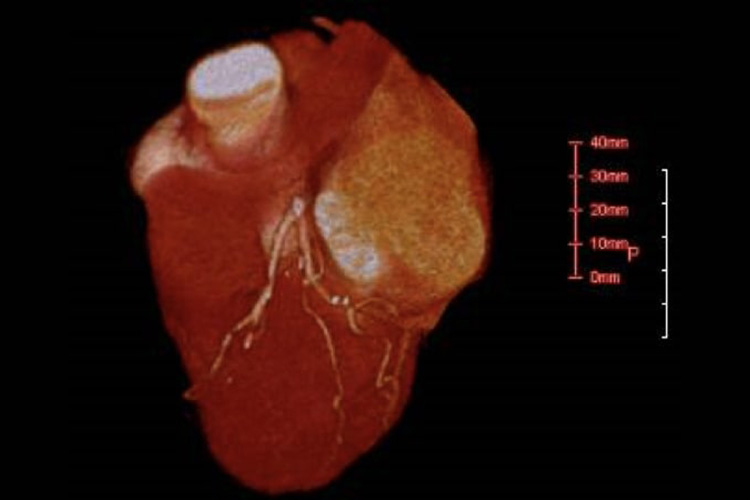

⑦冠動脈CT検査

造影剤を静脈注射し、心電図と同期させながらCTをとることで、冠動脈狭窄の有無を診断します。短時間で心臓の断面を撮影し、三次元画像で表わすことが可能です。但し脈の速い方や不整脈のある方、冠動脈石灰化が強い方では評価が難しい場合もあります。